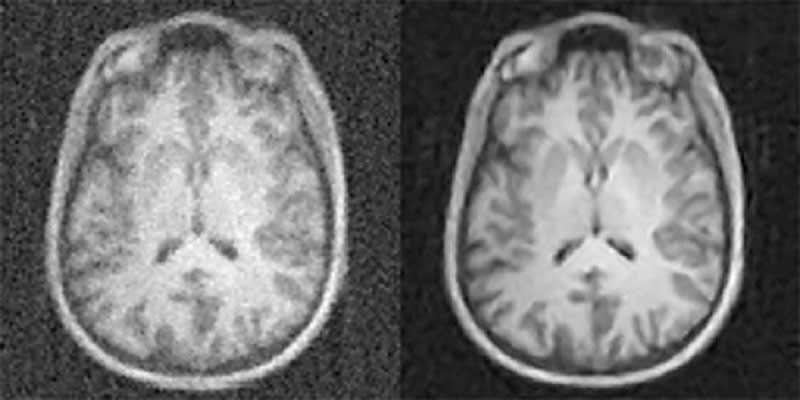

A radiologist's ability to make accurate diagnoses from high-quality diagnostic imaging studies directly impacts patient outcome. However, acquiring sufficient data to generate the best quality imaging comes at a cost – increased radiation dose for computed tomography (CT) and positron emission tomography (PET) or uncomfortably long scan times for magnetic resonance imaging (MRI). Now researchers with the Athinoula A. Martinos Center for Biomedical Imaging at Massachusetts General Hospital (MGH) have addressed this challenge with a new technique based on artificial intelligence (AI) and machine learning, enabling clinicians to acquire higher quality images without having to collect additional data. They call the technique automated transform by manifold approximation or AUTOMAP.

"An essential part of the clinical imaging pipeline is image reconstruction, which transforms the raw data coming off the scanner into images for radiologists to evaluate," says Bo Zhu, Ph.D., a research fellow in the MGH Martinos Center. "The conventional approach to image reconstruction uses a chain of handcrafted signal processing modules that require expert manual parameter tuning and often are unable to handle imperfections of the raw data, such as noise. We introduce a new paradigm in which the correct image reconstruction algorithm is automatically determined by deep learning AI.

"With AUTOMAP, we've taught imaging systems to 'see' the way humans learn to see after birth, not through directly programming the brain but by promoting neural connections to adapt organically through repeated training on real-world examples," Zhu explains. "This approach allows our imaging systems to automatically find the best computational strategies to produce clear, accurate images in a wide variety of imaging scenarios."